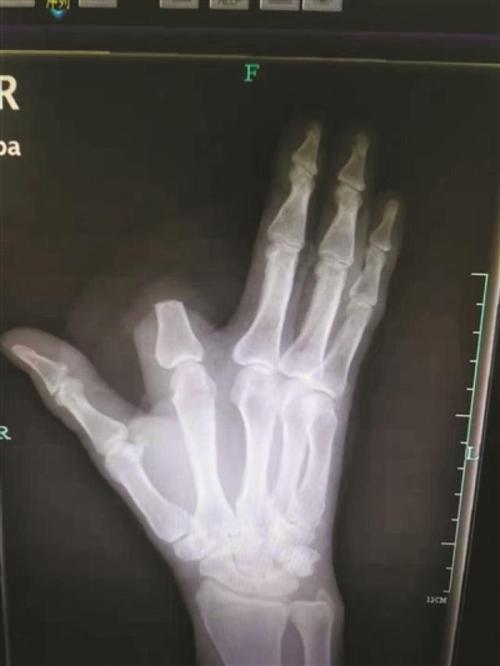

x光照片手

x光照片手,x光照片

患者的x光片.图片由杭州市中医院提供

手指x光片

x光手骨正常照片

手部x光图片

正常右手x光片图片

正常人手x光图片

x光手骨

手掌x光

正常右手x光片